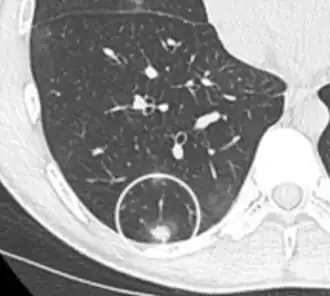

- A lung nodule abutting a pulmonary cyst is a rare finding, yet indicating cancer.[9]